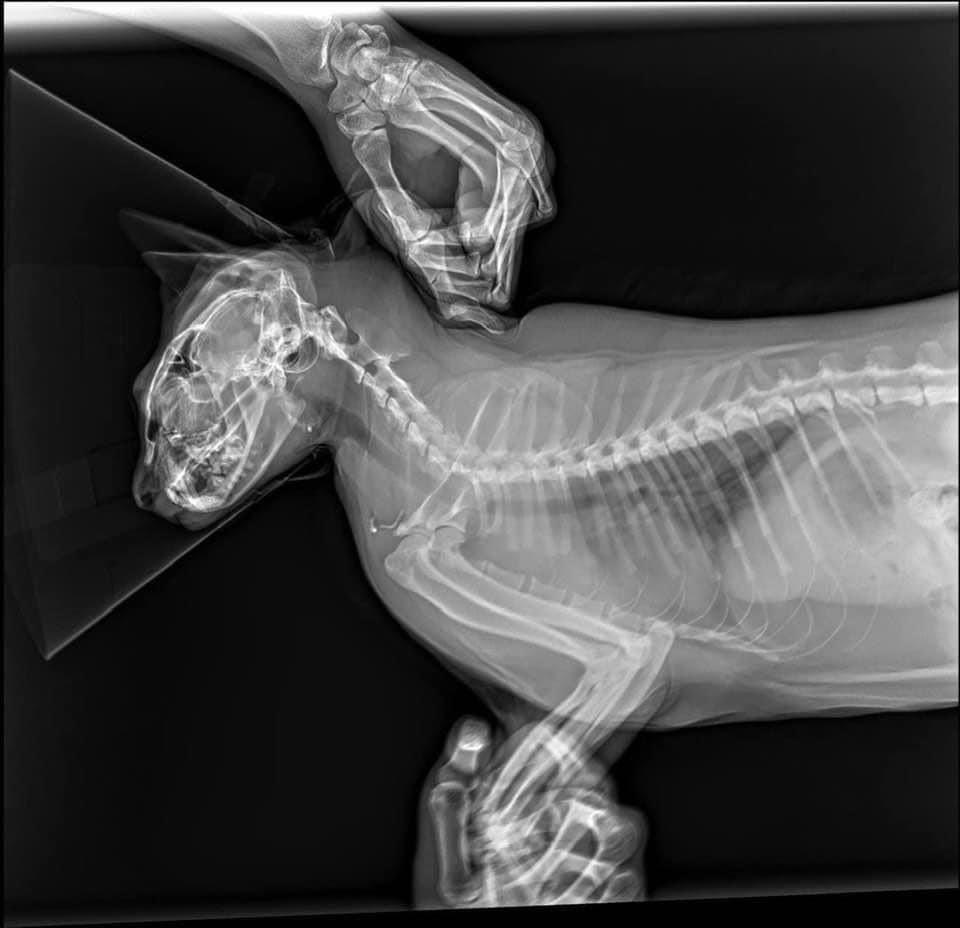

Sáng Chủ nhật đang ngủ ngon lành thì bảo vệ gọi xuống kiểm tra xe, bác còn bảo có con mèo bự làm hư xe, nghe mơ hồ như chiêm bao vậy, cho đến khi xuống xem mới biết. Bà mèo này nặng 8,5kg "hạ phàm" từ trên tầng xuống và làm vỡ kính xe. ![]()

Không chỉ vậy, giờ không tìm ra ai là chủ của nó, nên phải đưa nó đi khám bác sỹ thú y, chụp chiếu các kiểu nhưng may là nó không bị gì, chỉ bị xước 1 tý móng chân, có lẽ do lớp mỡ dày quá chăng?